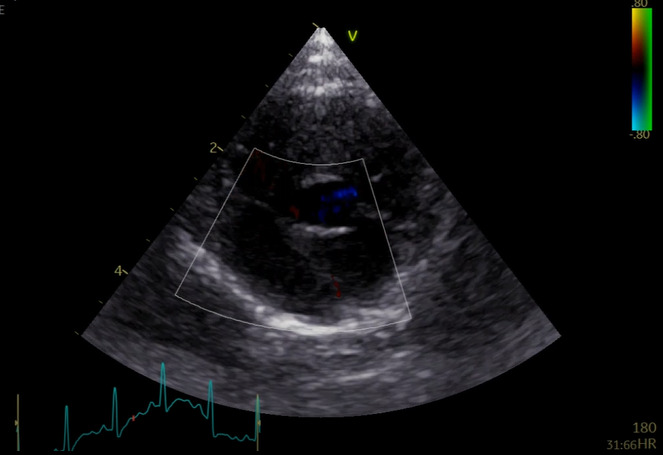

図3C 心原性肺水腫の猫における肺超音波画像

雑種猫、8歳5カ月齢、去勢雄、体重4.68kg。心疾患の管理中であったが、3日ほど投薬できておらず、かかりつけ医より紹介来院した。肺水腫によりB-lineの増加(white lung)が認められた。

特集 悩ましい猫の肺炎 vs. 肺水腫 vs. 肺腫瘍(塗木貴臣先生)図3Ⅽ